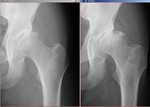

[画像診断]急速破壊型関節症のX-ray 2010-04-13